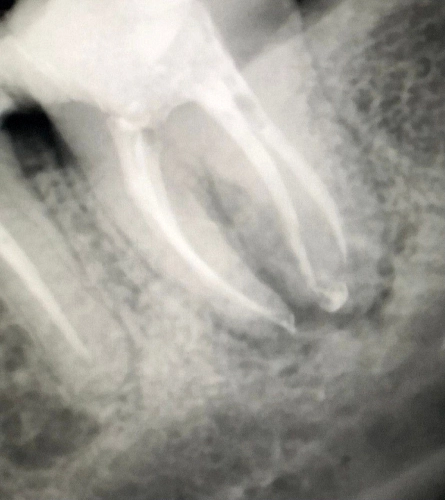

Пациент обратился с жалобой на боль при накусывании и ноющую боль в зубе.

На диагностическом рентгеновском снимке был обнаружен очаг деструкции костной ткани в области данного зуба, так же не полностью запломбированные каналы и отломок инструмента в одном из корневых каналов.